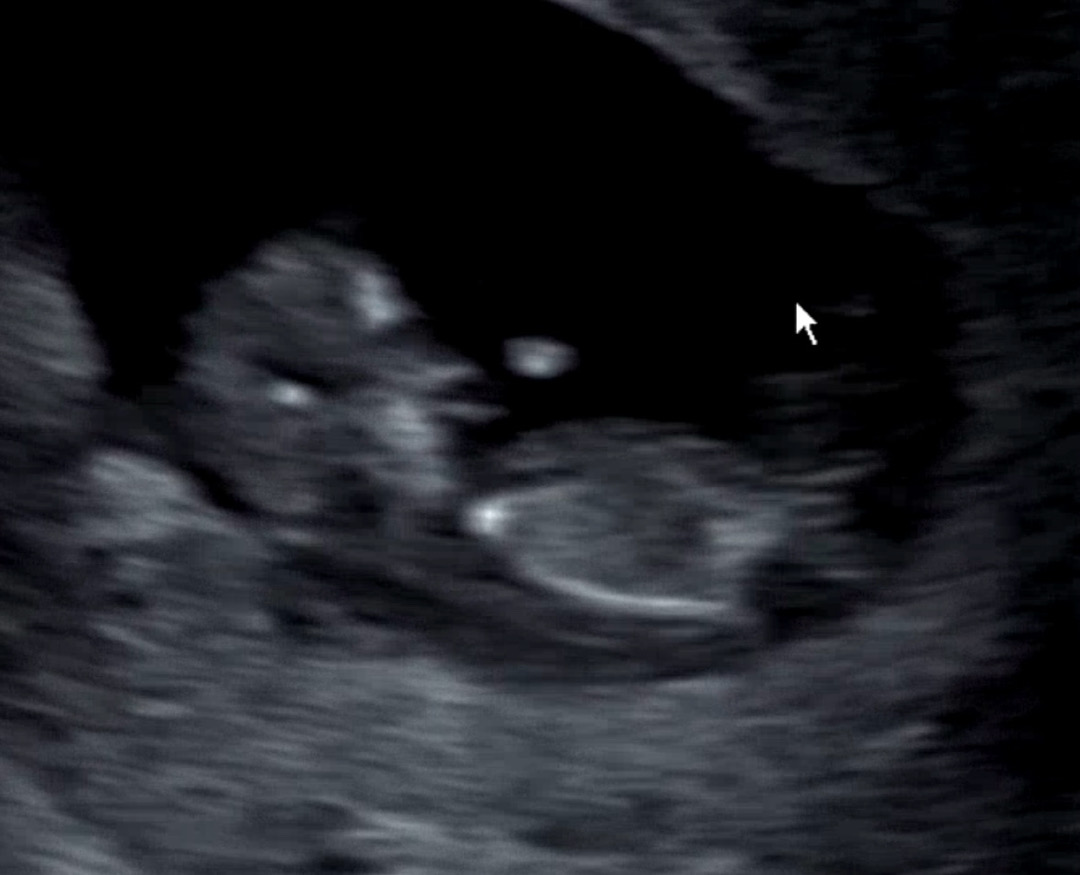

혹시...각도법 잘 보시는 분 계실까요❤️

안녕하세요! 다들 점심은 맛있게 드셨나요? 아직 성별을 알기에 이르다는걸 잘 알고 있지만 그치만 너무너무너무 궁금해요 흐어엉😭 저는 아들이든 딸이든 그저 건강하기만 하면 된다라는 생각이구요, 혹시 지금 초음파 사진으로도 각도법 확인이 가능할지 질문 드려봅니다✨